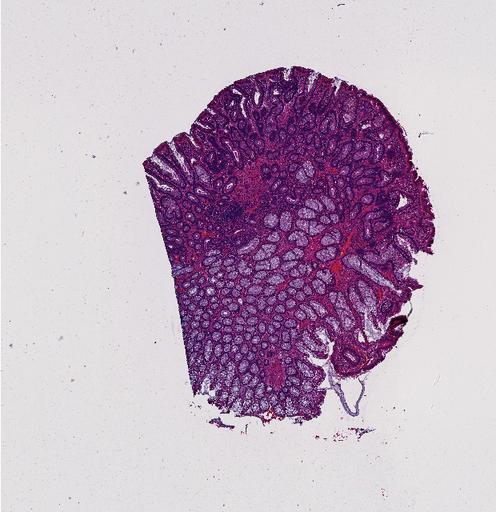

High‑resolution three‑dimensional (3D) tissue atlases promise to redefine how we study cellular architecture‑function relationships in human tissues. Large-scale consortia such as the Human Bimolecular Atlas Program (HuBMAP) systematically build detailed 3D organ maps by profiling serial tissue sections with single-cell spatial technologies. However, an accurate and efficient reconstruction method that can handle atlas-scale datasets remains elusive. We introduce Space-map, an open-source method that integrates single‑cell coordinates with optional histological image features to assemble serial sections into 3D models. Space‑map combines multi‑scale feature matching with large‑deformation diffeomorphic metric mapping, delivering global reconstructions while preserving local micro‑anatomy. To demonstrate the capability of Space-map, we generated a serially sectioned spatial transcriptomics (Xenium, ~2.9M cells) dataset and a spatial proteomics dataset (CODEX, ~2.4M cells). Applying Space-map to these single-cell spatial maps, we built three 3D models for both diseased (colon polyp) and reference colon tissues. These high-resolution 3D models showcase the intricate structure of the human colon across different states. Space-map is fast and highly efficient. We demonstrated its performance and accuracy using in‑house and public datasets. The result shows that Space‑map is 10 times faster and ~2‑fold more accurate than PASTE and STalign, making 3D atlas reconstruction more accessible. Our study provides a new robust and user-friendly software available at https://github.com/a12910/spacemap that can be easily applied for constructing molecular 3D tissue maps of human organs at single-cell resolution.